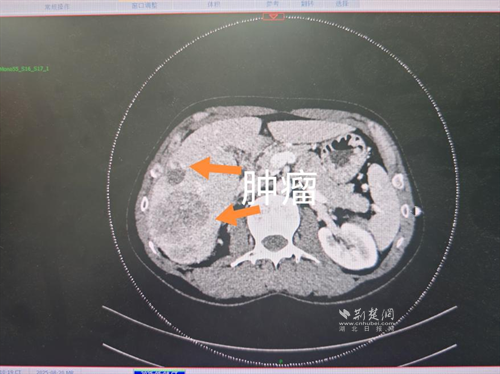

經(jīng)過肝膽外科牽頭組織的多學(xué)科MDT會診,團(tuán)隊確認(rèn)其適合接受當(dāng)前國際先進(jìn)的釔90樹脂微球選擇性內(nèi)放射治療。治療僅一個月后,患者病灶即從10cm縮小至6cm;術(shù)后六個月復(fù)查顯示,病灶體積進(jìn)一步縮小近40%,影像學(xué)檢查提示完全緩解,臨床分期成功轉(zhuǎn)化,達(dá)到手術(shù)切除標(biāo)準(zhǔn)。